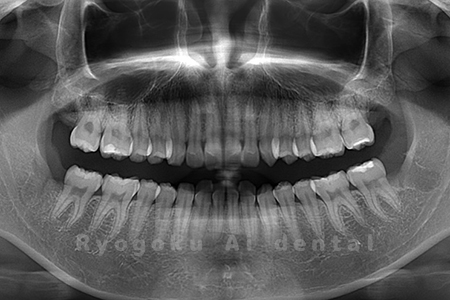

Case03

-

- 原因

- 上顎、下顎の親知らず

- 治療内容

- 上下4本の親知らずを抜歯したケースです。

<リスク・副作用>

手術後は痛み、腫れ、痺れなどの副作用が生じる場合があります。